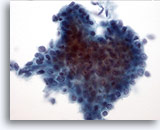

Figure 30

Breast FNA, Ductal carcinoma.

This low-power field shows abundant cellular necrosis with a tight cluster of cells in the center from a case of invasive ductal carcinoma. 20x

Figure 30

Breast FNA, Ductal carcinoma.

This low-power field shows abundant cellular necrosis with a tight cluster of cells in the center from a case of invasive ductal carcinoma.

20x